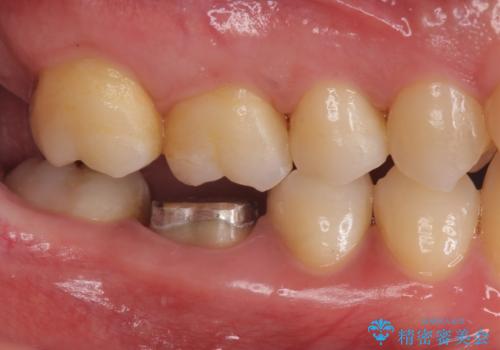

下の奥歯は口を開くと簡単に外から見えてしまいます。

銀色だった歯が白くなったことで大変喜んでいただけました。